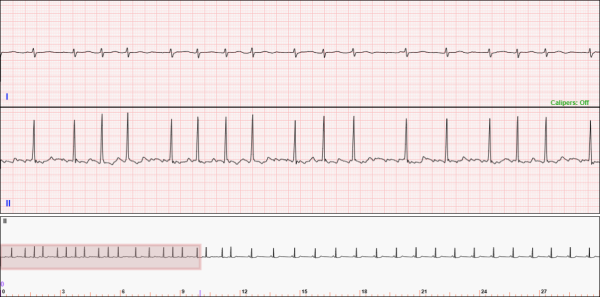

Fig. 1: The 1-lead long telemetry ECG UI. Notice the single Analysis Window on top and the Navigation Window on the bottom.

Fig. 2: The 2-lead long telemetry ECG UI. Notice the two Analysis Windows on top and the Navigation Window on the bottom.

Figures 1 through 3 show examples of the ECG displays for the 1-lead, 2-lead, and 3-lead long telemetry ECGs. The interface consists of two regions.

• The Analysis Windows: the top region(s) of the ECG display

• You will use these region(s) to interact with the ECG using calipers

• Shows the portion of the ECG contained in the Navigation Box located in the Navigation Window

• The Navigation Window: the bottom region of the ECG display

• You will use this region to zoom in and out on and to move around the entire ECG

• The Navigation Window shows the entire telemetry strip at a lower resolution.

• Use this region get a view of the entire ECG